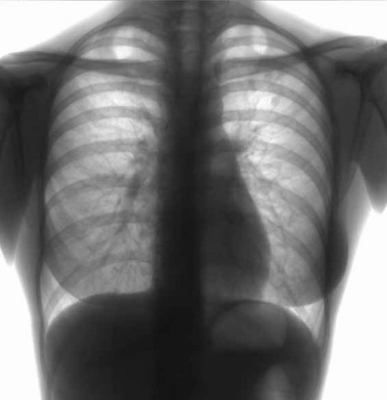

Так, по сравнению с аналогичным периодом 2013 года на 28,5% снизился общий уровень заболеваемости туберкулезом, на 30,1% заболеваемость туберкулезом органов дыхания, в том числе с бактериовыделением на 20,1%. Снизился и уровень заболеваемости активным туберкулезом среди детей. В первом полугодии 2014 года выявлено 14 детей с активными формами туберкулеза, за аналогичный период 2013 года — 29.